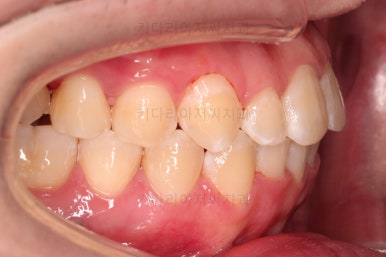

부산교정치과 초진 시 입안의 모습입니다.

앞니가 삐뚤어서 결손치아가 없었더라도 교정치료를 원하셨던 상황이었고요.

오른쪽 어금니 맞물림은 결손치아도 그렇지만 전반적인 앞뒤 차이가 있는 부정교합이 있었어요.

얼굴모습인데요.

전반적인 입매는 나쁘지 않아 굳이 입을 더 넣거나 뺄 필요는 없어보이고요.

웃을 때 정렬되지 못한 치열 때문에 미적으로 좋지 못하네요.